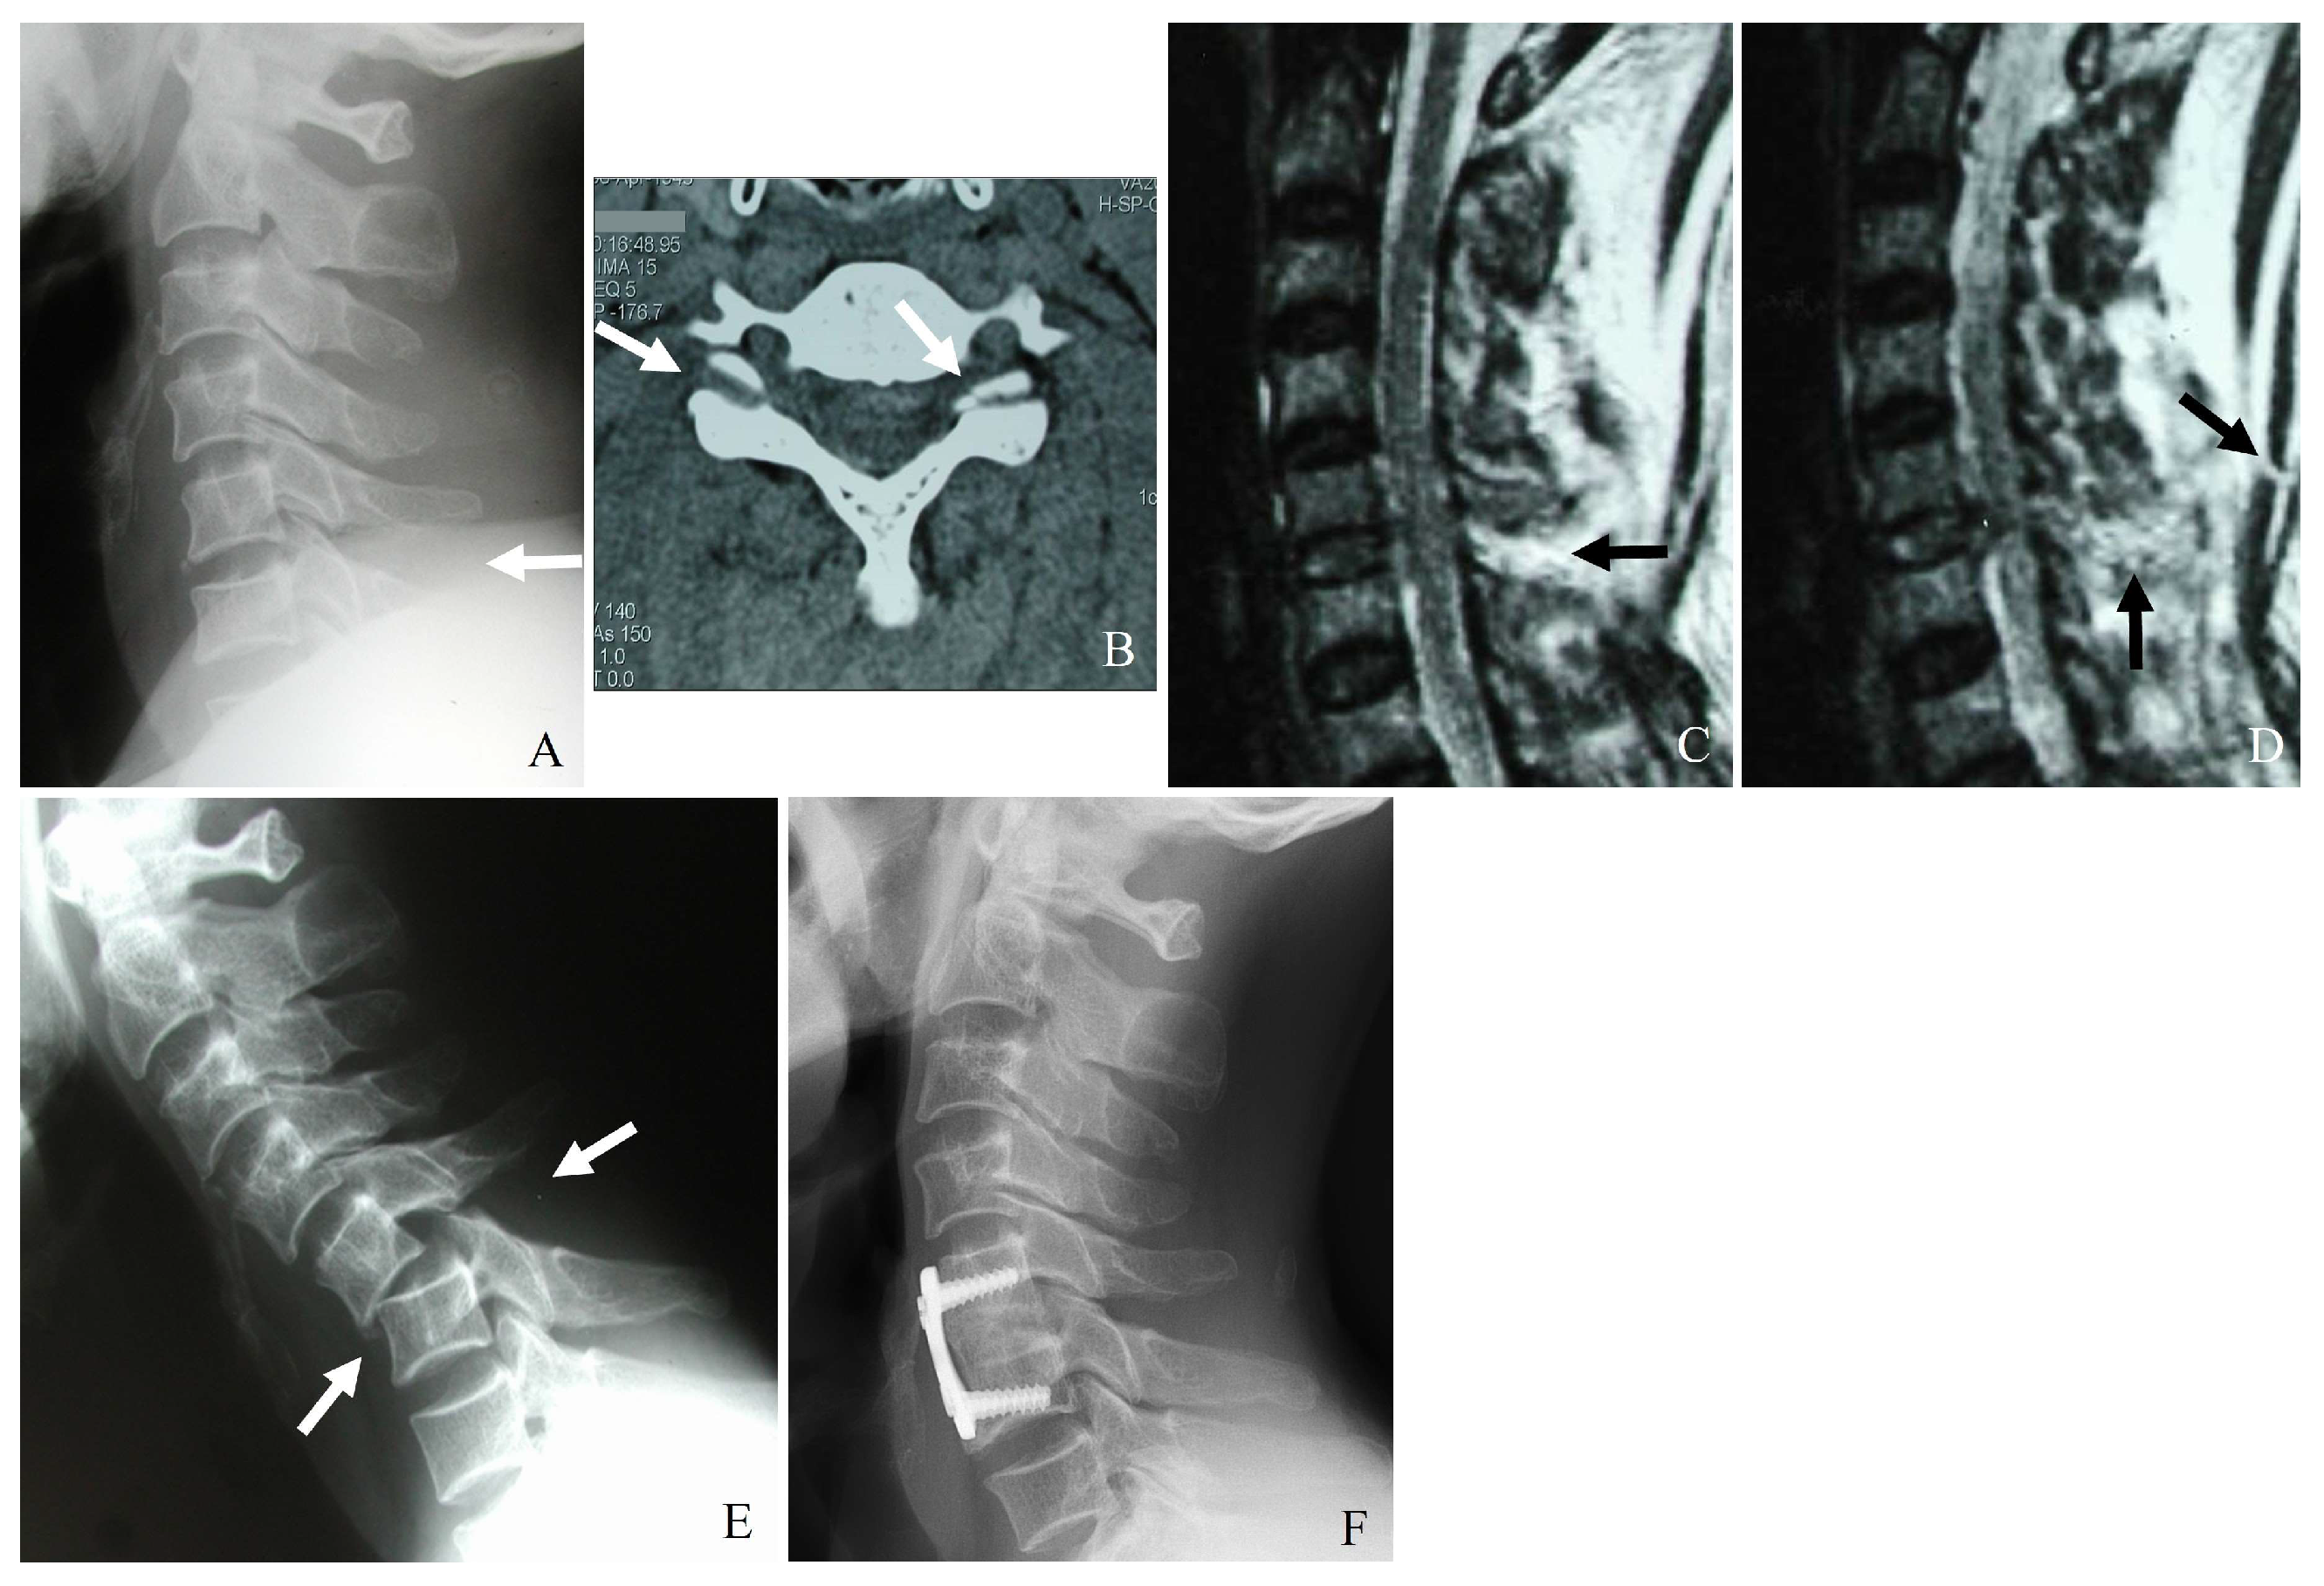

3.1. Plain Radiography

3.2. Computed Tomography (CT)

3.3. Magnetic Resonance Imaging (MRI)